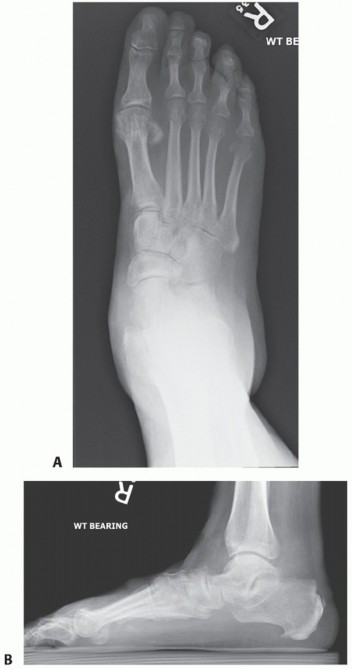

DEFINITION Symptomatic hallux valgus associated with a first intermetatarsal angle greater than 15 degrees is…